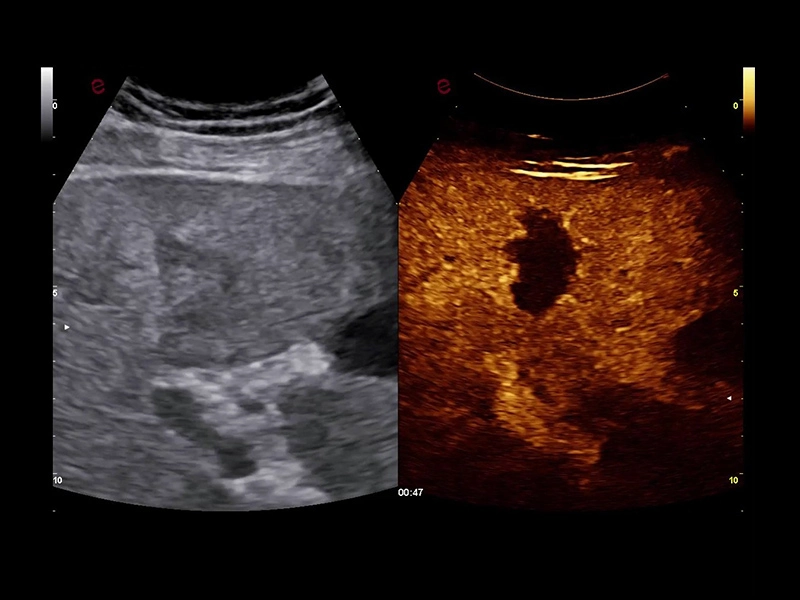

MyLab™E80 - CEUS - Liver

MyLab™E80 - CEUS - Liver

MyLab™9 Platform - QPack CnTI™ perfusion analysis post RF ablation

MyLab™9 Platform - QPack CnTI™ perfusion analysis post RF ablation

MyLab™X8 Platform - Contrast session with CnTI™ and Q-Pack

MyLab™X8 Platform - Contrast session with CnTI™ and Q-Pack